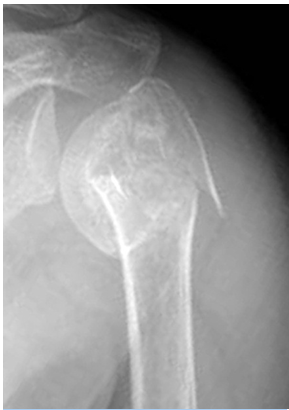

근위 상완골 골절이란?(Proximal humerus fracture)

근위 상완골 골절은 어깨 근처, 상완골의 상부에서 발생하는 골절을 말합니다.

이는 특히 노인 인구에서 많이 발생하는 골절 유형으로, 낙상시 손으로 지지하는 경우 어깨 부위에 가해지는 충격으로 인해 발생할 수 있습니다.

진단 방법

물리적 검사: 의사는 부상 부위의 통증, 부기, 변형을 평가합니다.

영상 진단 검사: X-ray, CT 스캔 또는 MRI를 통해 골절의 정확한 위치와 정도를 파악합니다.